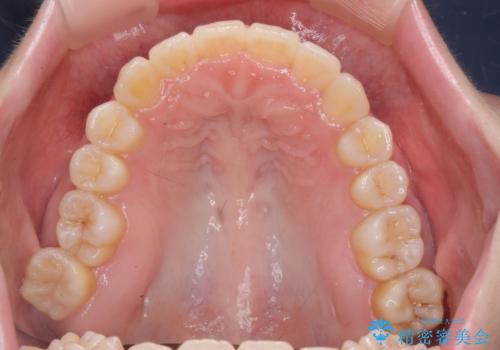

サクソフォン(アルト)の演奏で崩れてしまった歯並び、マウスピース矯正治療

口腔内の清掃状態の良さに加えて、マウスピースを毎日きっちりと装着し、しっかりと使用していただけたことからワイヤー矯正は行わずにきれいに歯並びを治すことができました。

途中顎位が変わり、マイクロインプラントを併用した上顎臼歯の遠心移動が必要となったため治療が長期化しました。